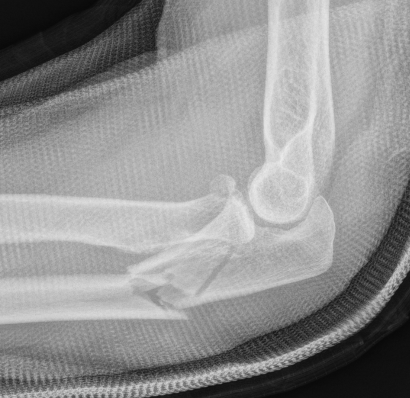

Simple Monteggia fracture - dislocations

Definition

Proximal ulna / olecranon fracture

- posterior radial head dislocation most common in adults

- no fractures

Bado Type II most common in adults with posterior radial head dislocation